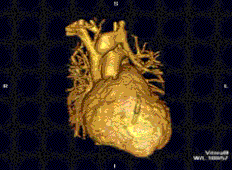

Cardiac magnetic resonance imaging (cardiac MRI, CMR), also known as cardiovascular MRI, is a magnetic resonance imaging (MRI) technology used for non-invasive assessment of the function and structure of the cardiovascular system.[2] Conditions in which it is performed include congenital heart disease, cardiomyopathies and valvular heart disease, diseases of the aorta such as dissection, aneurysm and coarctation, coronary heart disease. It can also be used to look at pulmonary veins.[3]

Cardiovascular MRI is complementary to other imaging techniques, such as echocardiography, cardiac CT, and nuclear medicine. The technique has a key role in evidence-based diagnosis and treatment of cardiovascular disease.[4] Its applications include assessment of myocardial ischemia and viability, cardiomyopathies, myocarditis, iron overload, vascular diseases, and congenital heart disease.[5] It is the reference standard for the assessment of cardiac structure and function,[6] and is valuable for diagnosis and surgical planning in complex congenital heart disease.[7]